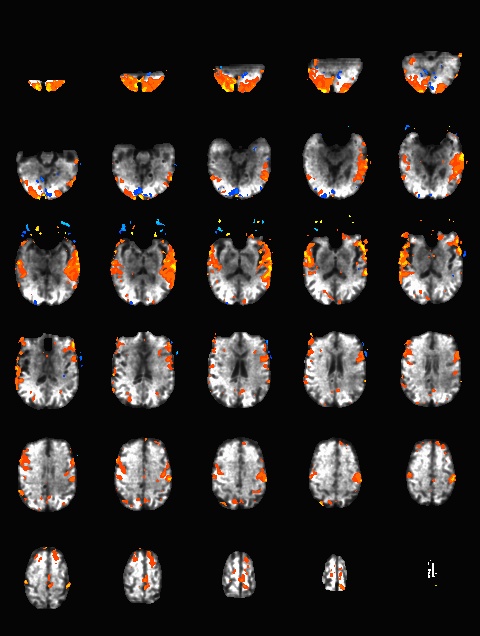

Now, desired intensity levels will be mapped appropriately to the screen. Rough calculation of image size in degrees of visual angle: roughly 76.5 cm from screen to eyeball height of screen is 13.7 in = 34. 8 cm width of screen is 34.8 * (1024/768) = 46.4 cm atan(23.2/76.5) = 0.29 rad = 16.6 degrees ~30 degrees full width Audio (headphones)Oneway to deliver auditory stimuli to your participants is through the headphones. These are Siemens equipment and are controlled by the scanner. First, make sure the headphone cord is plugged into to your stimulus presentation computer (laptop, desktop, boombox, etc). Then, plug the other end into the back of the intercom box (the same one that's used to speak with the participant while they're in the scanner.) If you're not hearing anything, go to Options -> Configuration. A new window will pop up with icons. Choose "Patient Comfort." In the next window, make sure the volume bars under "Music" are not at the very bottom (which is the default.) . The speaker icon indicates sounds send to the room, and the headphone bar is specific to sound sent through the headphones. ASL HelpThis ppt describes the units when you draw an ROI on the relCBV map (BW). You cannot draw on the Perfusion Color map the units are not scaled. Media:ASL.ppt Quality AssuranceWeekly QA scans are performed on both the Prisma and Trio scanners. Below are the results of the previous 52 week EPI QA runs.